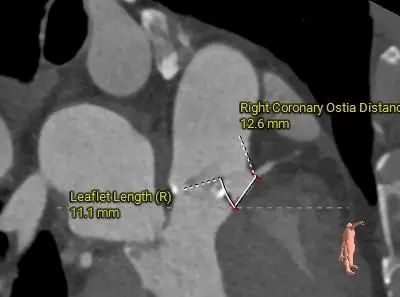

冠脉评估:

左冠开口高度较低,瓣叶略冗长

根部结构较小,冠脉阻挡风险偏高